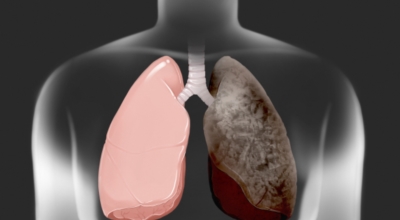

폐에 발생된 악성 종양을 말하며 오랜 기간 흡연해온 남성들에서 발병률이 높고 최근 들어 가지가지 환경적인 요인의 영향과 간접흡연으로 흡연하지 않는 여성에서도 많이 발생하고 있어요. 증상을 느껴 병원을 찾았을 때는 수술하기 늦은 경우가 많아 사망하는 비율이 매우 높은 암입니다. 폐 자체에서 생기거나 다른 장기에서 발생된 암이 폐로 전이되어 나타나기도 하고 특별한 초기 증상이 없는 경우가 많다고 하며 암이 진행된 후에도 일반적인 감기 증상인 기침과 가래 외의 특이 증상이 나타나지않아 증상만으로는 진단이 쉽지 않아요.

폐암의 공통 위험요소로 손꼽히는 까닭으로 흡연이 있어요. 흡연자는 비흡연자에 비교해 십몇 배는 더 폐암 발병확률이 높다고 하며 어느정도 기간 동안 흡연했는지에 따라 폐암 발생확률은 더욱더 더 높아져요. 흡연자라고 해도 금연을 하게 되면 폐암 발병확률이 가파르게 감소한다고 하니 폐암이 걱정되신다면 가장 먼저 금연은 필수입니다.